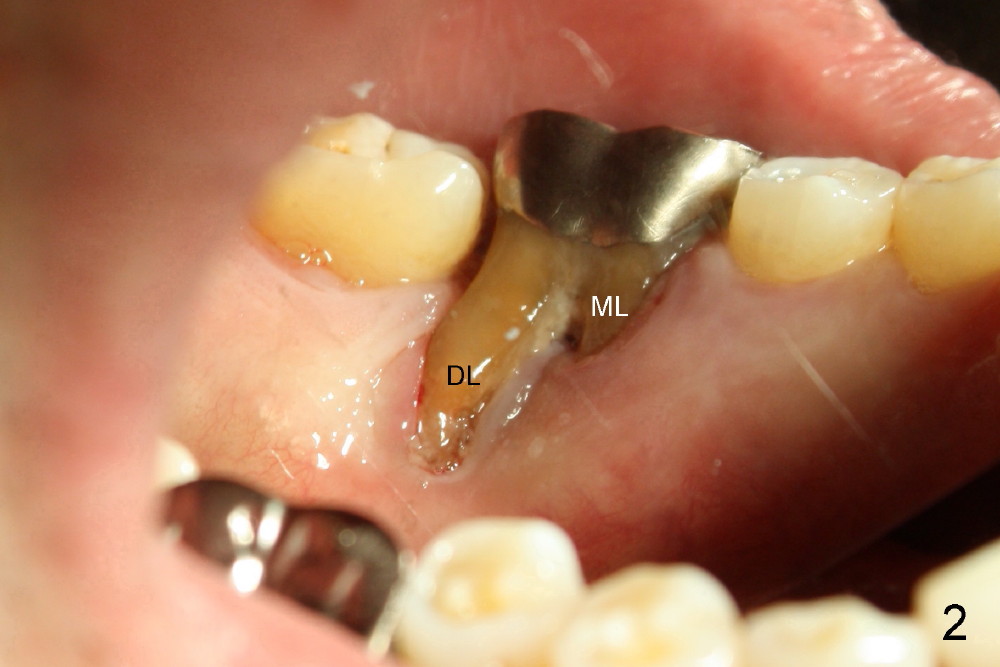

A 61-year-old man has severe periodontal disease. The lower right first molar is compounded by endodontic lesion. The distobuccal (Fig.1 DB) and distolingual (Fig.2 (mirror image) DL) roots are exposed.